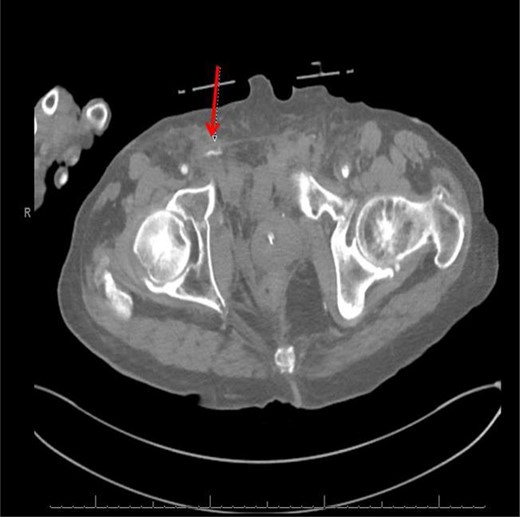

CT abdomen/pelvis with contrast was performed and a blush of contrast was noted posterior to the right pubic bone. Prior to taking patient for exploratory surgery, he was transferred to the interventional radiology suite where a pelvic angiogram was performed revealing an abnormal blush localized to the distal branches of the right iliolumbar artery (Fig. 2). Delayed phase of the angiogram demonstrated early venous filling consistent with a traumatic arteriovenous fistula which was embolized with 300–500 µ of embospheres and three 3 × 2 microcoils (Figs 3 and 4).

CT angiogram demonstrating microcoil embolization of AV fistula.